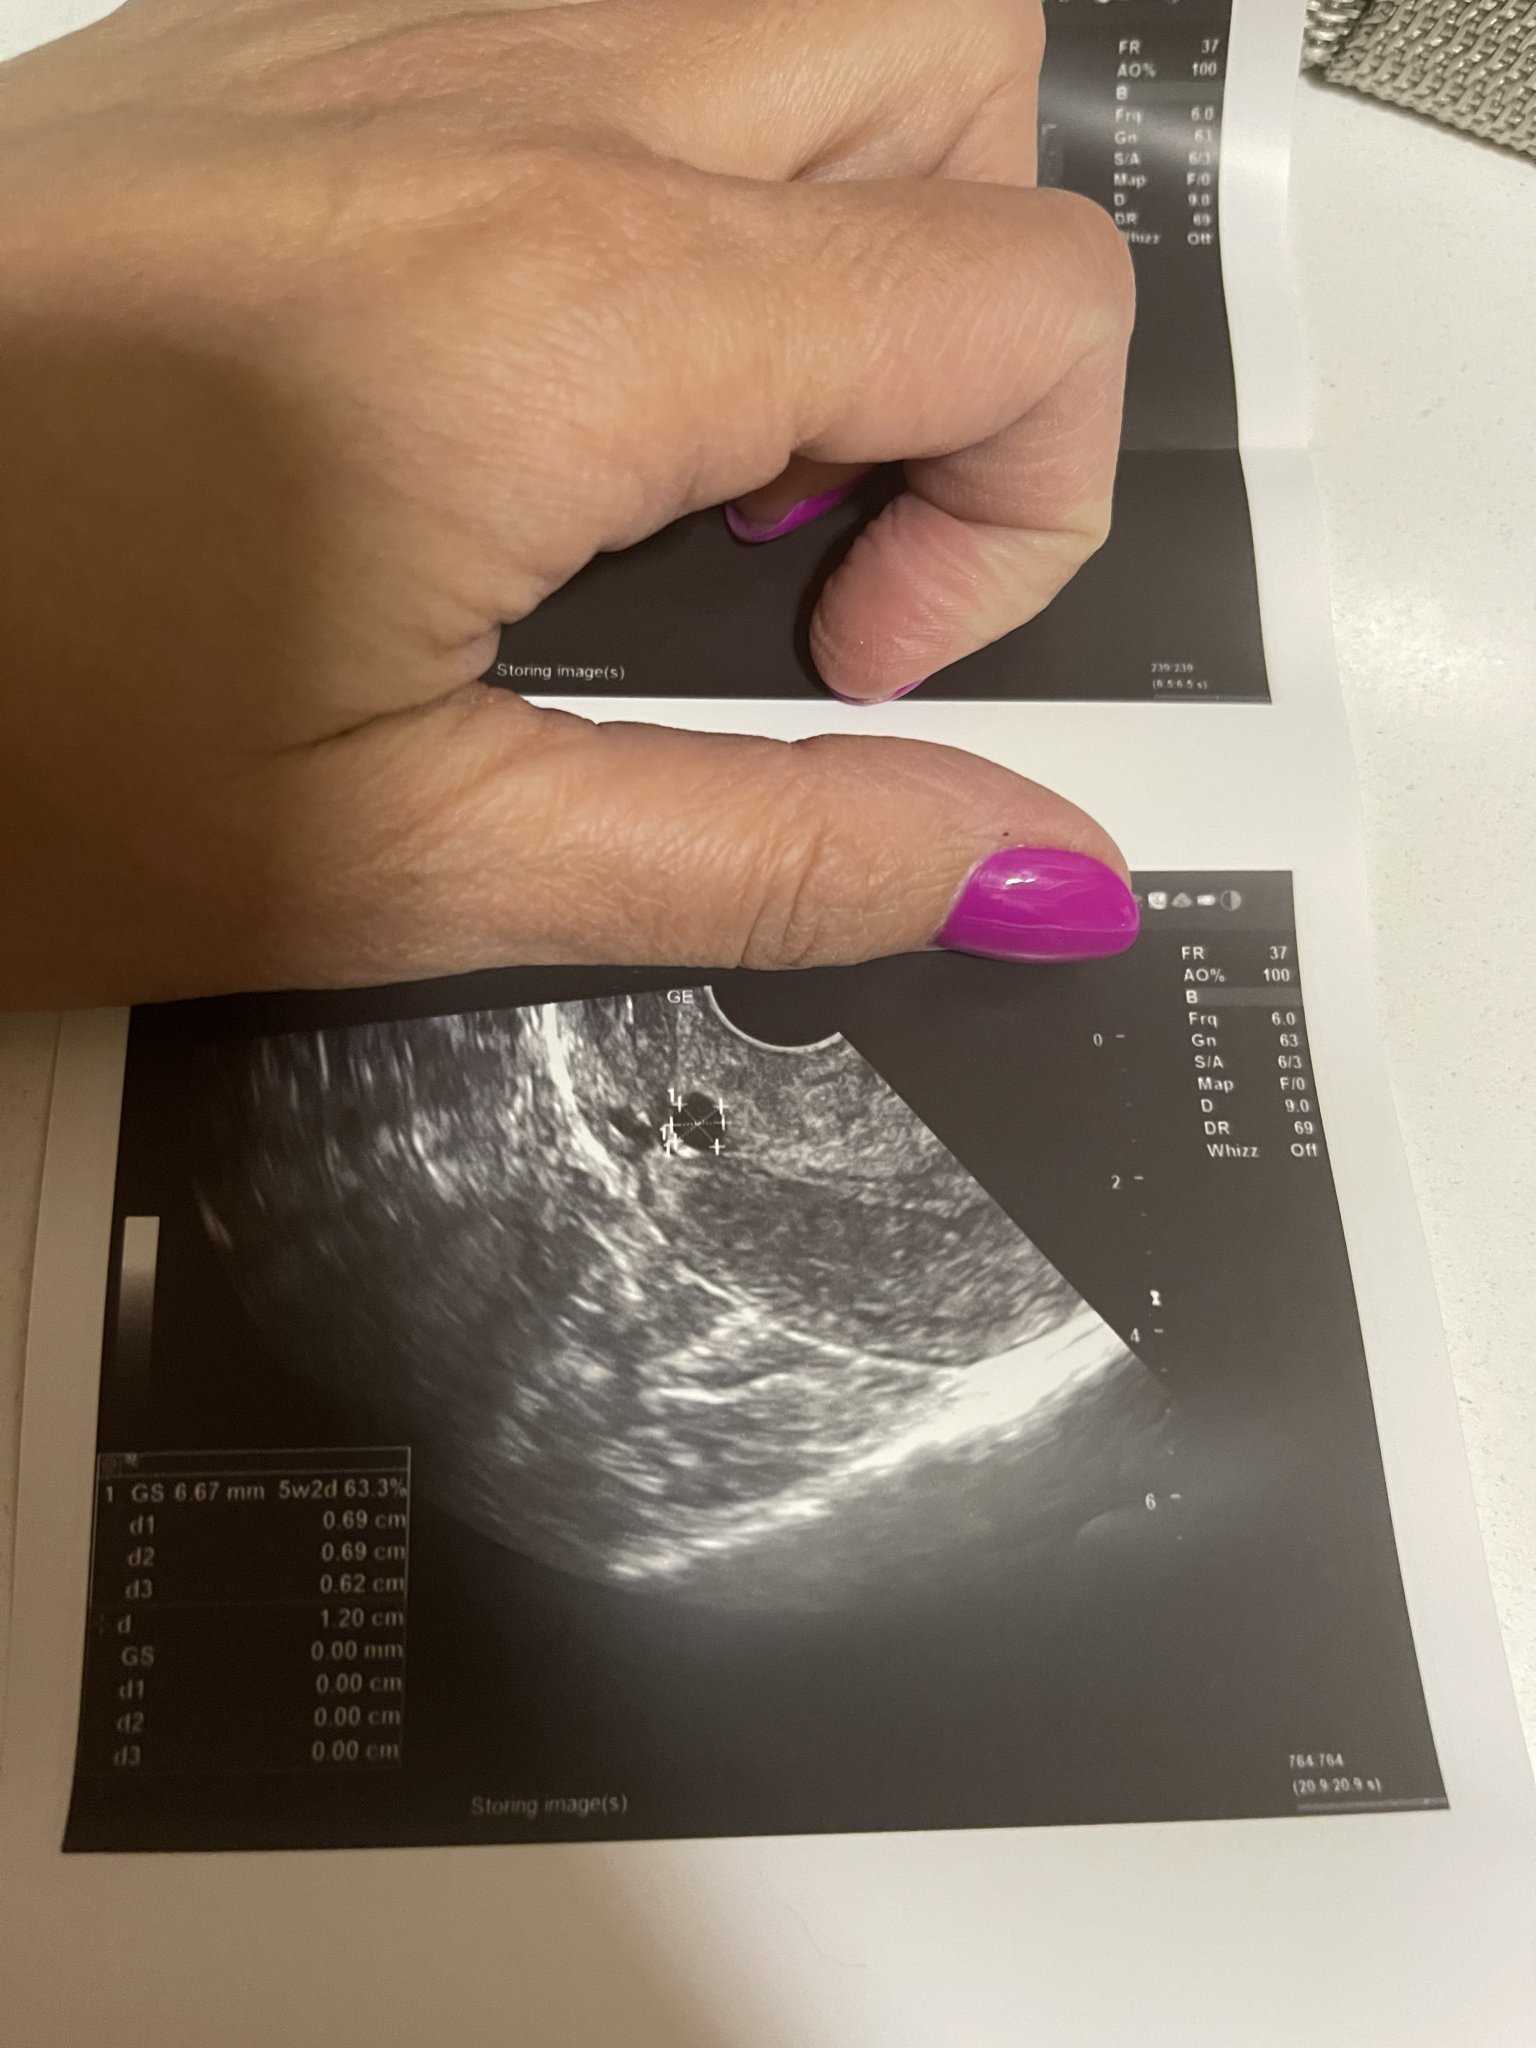

Аз пак съм в тъмни мисли и отчаяние. Днес поради болки ниско долу отидох в спешен кабинет  в столична болница, защото доктора ми не е на работа уикенда и ме насочи натам. Отговор защо имам болки бе това, че имам сраствания, а в матката не виждат “хубава” бременност. Ще приложа снимки на това, което виждат и не знаят какво е. Казаха ми да направя ново ЧХГ, но в тази лаборатория методиката им е друга и има разминаване в стойностити от лабораторията, където пусках всички останали. Нямам кървене, имам симптоми, имам и много объркващи мисли какво се случва, извънматочна бременност, биохимична или какво?!..

Пусни след два дни пак ЧХГ. На снимката все пак се вижда точка, при мен беше такава. После се превърна в малко ембрионче с пулсиращо сърчице и вече съм в 10 г. с. Не искам да ти давам фалшиви надежди, но защо да не е тая точица бъдещото ти бебче?

при тази ниска стойност на ЧХГ не се визуализира бременност все още, обикновено това става след 1000. Сигурно има и изключения, но това като цяло е информацията, която имам от АГ и от нета. И все пак проследете наистина ЧХГ след още 2 дни. Обикновено в началото нараства доста бързо и до 10ина дни закъснение достига четирицифрени стойности.

При мен нещата приключват, днес бях на преглед отново понеже се появи зацапване и болки. Плоден сак видяха(отговаря на 5г.с.) много ниско до разреза на предишната операция, но ЧХГ се е понижило до 49.88. Сега ми остана да чакам цикъл или ако прокървя да отида веднага.